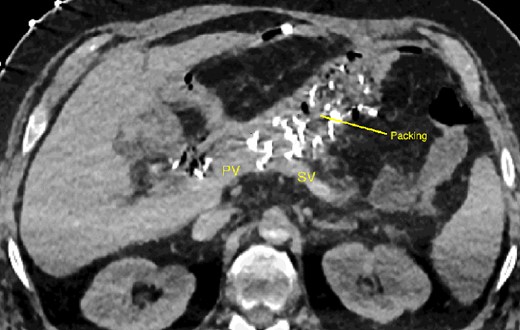

A 52-year-old man with a past medical history of obesity, diabetes, and Lynch syndrome, which had led to a subtotal colectomy 4 years earlier, underwent an open pancreatoduodenectomy for a duodenal adenocarcinoma in the tertiary referral center. The pancreas had a soft texture; hence, a pancreaticogastrostomy anastomosis was performed. No vascular resection or reconstruction was necessary. Multi-tubular drains were placed behind the anastomoses (pancreaticogastrostomy and hepaticojejunostomy) at the end of the procedure. Six days after surgery, the patient developed sepsis due to a pancreatic fistula (grade B, according to ISGPS definition) [4]. The patient was treated with intravenous antibiotics. On the fifteenth postoperative day, we noticed bleeding through the drain orifice (about 400 cc) that stopped spontaneously. The patient was hemodynamically stable, and no active bleeding or arterial pseudoaneurysms were found on a computed tomography (CT) scan. On the twentieth post-operative day, the hemorrhage recurred and ceased spontaneously again. The CT scan showed a splenic vein irregularity without active bleeding or intra-abdominal free fluid (Fig. 1). After a massive new bleeding the same day, we performed an exploratory laparotomy.

20-day post-operative CT scan showing irregularity of the splenic vein, without active bleeding. PV portal vein, SV splenic vein, D multi-tubular drain.